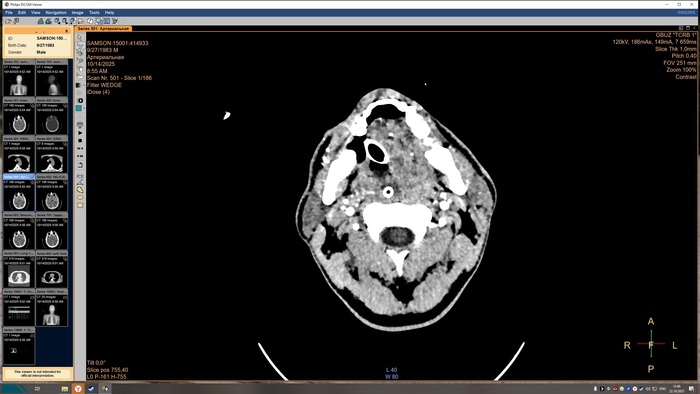

Описание КТ прикрепляю, а снимки будут в конце поста, по-другому у меня не получилось.

На топограмме, серии аксиальных срезов и реконструкций получены изображения суб- и

супратенториальных структур головного мозга от большого затылочного отверстия до крыши

черепа в нативном виде и в/в контрастированием. Определяются: справа четко

идентифицируемые внутричерепные интрапаренхиматозные гиперденсные неоднородные

очаги, копящее контрастное вещество, плотностью до 51-55ед.Х., размером: в проекции

лучистого венца 8х8х9 мм, в проекции продолговатого мозга 21х26х19 мм, Срединные

структуры мозга не смещены. Боковые желудочки: правый до 10,2 мм, левый до 12,9 мм,

третий-2,6 мм, четвёртый-13,8 мм. Селлярная и хиазмальная области без видимых

патологических изменений. Цистерны основания мозга, конвекситальные ликворные

пространства и борозды полушарий большого мозга сужены. Оболочки мозга без

особенностей. Миндалины мозжечка расположены соответственно возрасту. Дополнительных

образований и жидкостных скоплений в воздухоносных полостях височных костей с обеих

сторон, полости носа и его придаточных пазух не выявлено. Содержимое глазниц

визуализируется без особенностей. Признаков остеолитического, -пластического процессов,

аномалий развития и/или травматических повреждений костей черепа исследованного уровня

Заключение

КТ-признаки очаговых образований головного мозга. КТ-признаки правосторонней

верхнедолевой сегментарной б/пневмонии. ДИ ГОП.

Снимки КТ